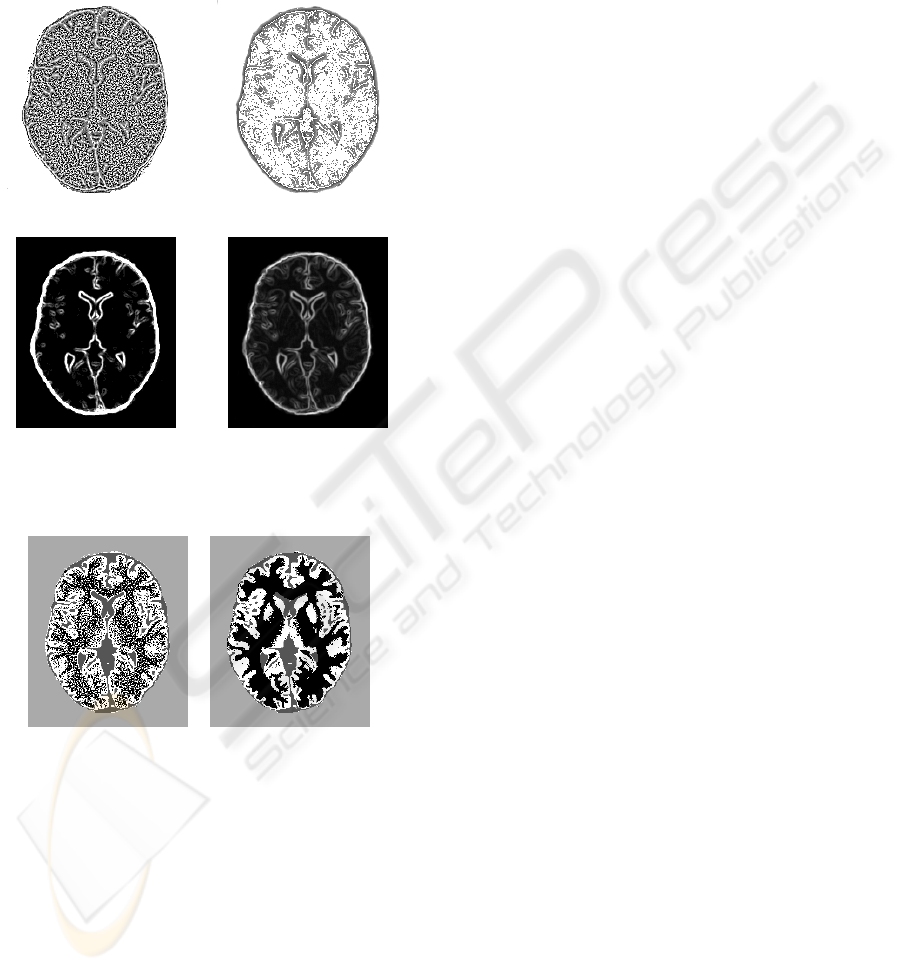

In the following, we present results from dataset

n9rf20 (figure 2) and use as LBP parameters R =

1.5,P = 12. All features were normalized by their

max value to cluster homogeneous values.